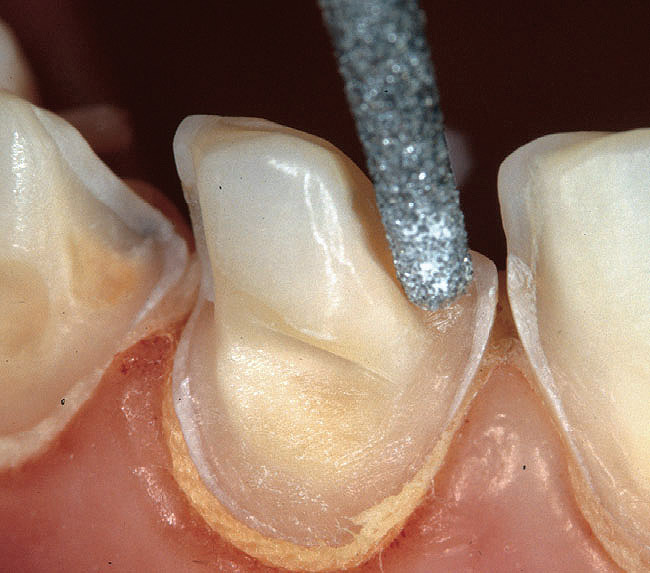

The next steps can include the application of either the primer (3-step systems) or the self-priming resin (2-step systems). Practically, the separate primer application should be favored (Figures 2H through 2J), not only because of the superior subsequent bond but also because it allows a more accurate placement of the adhesive resin. In fact, the application of a priming agent or self-priming resin often requires a slight brushing motion, which frequently results in the spread of resin above the exposed dentin limits. There are no consequences when using a separate primer as the latter does not create any detectable thickness or layer. After the suction of the excess solvent (Figure 2J), the adhesive resin can be placed accurately (eg, with a periodontal probe, as in the case of veneer preparation margins [Figures 2K through 2N). On the other hand, the use of self-priming resins generates excesses and may pull over the margin (into the gingival sulcus), requiring additional corrections with a bur, again exposing dentin at the margin.

Figure 2k  The adhesive is applied  with precision using a drop of resin on  the tip of a periodontal probe. Direct contact  between the dentin and the tip of the probe  should be avoided. The probe is used to  help spread the adhesive to the edges of  the exposed dentin.

Figure 2k

Figure 2l  The adhesive is left  to diffuse along the chamfer. The tip of the  probe should not approach the margin more  than 0.5 mm to avoid pulling of the resin (red  rectangle shows a magnified view of gingival  dentin margins seen in image M).

Figure 2l

Figure 2m  Because  of surface tension phenomenon, the  adhesive spreads onto the primed dentin  surface but is arrested at the sharp edge of  the margin.

Figure 2m

Figure 2n  Because of the original deep  chamfer, the definition of the margin is not  affected by the presence of the adhesive  laye.

Figure 2n